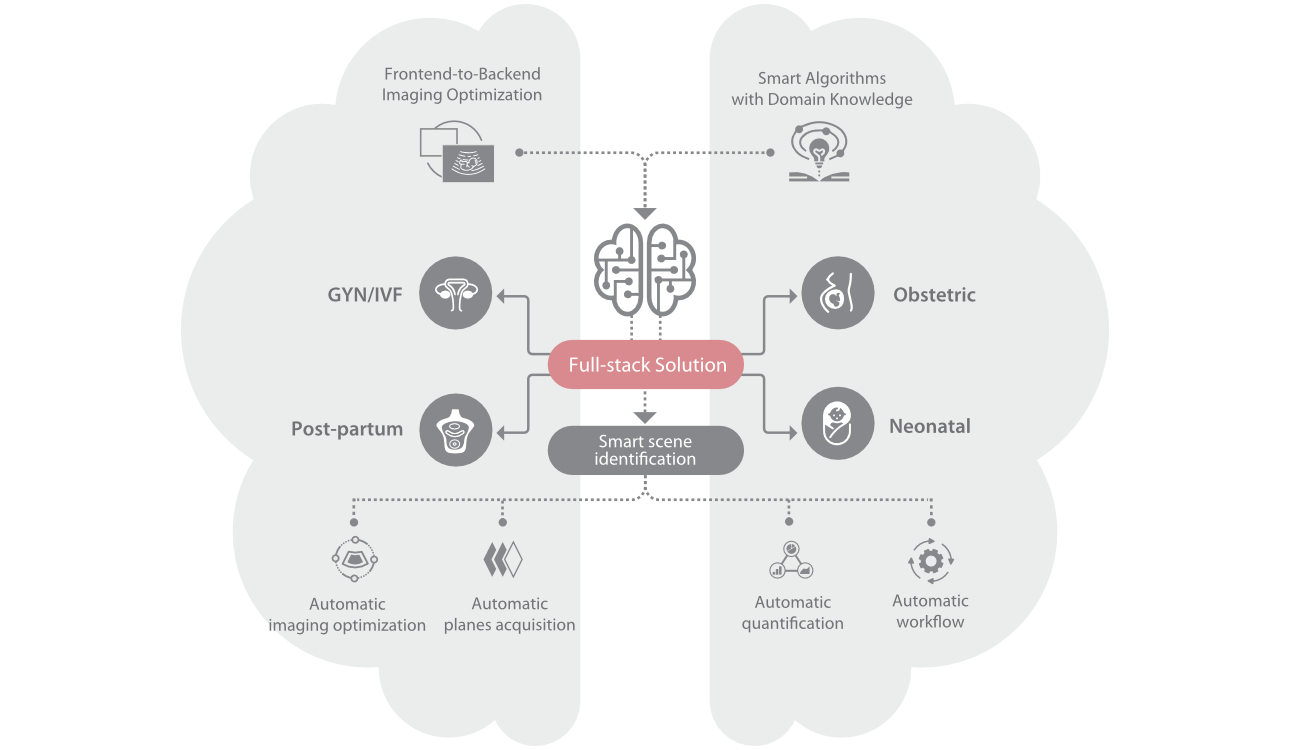

Full-stack Solution Powered by ZST?+

The ZST+ platform is an extraordinary innovation, representing an ultrasound evolution. Transforming ultrasound metrics from conventional beam-forming to channel data based processing. It overcomes the traditional trade-off limitation among spatial resolution, temporal resolution and tissue uniformity, delivering exceptional image quality for infinite imaging solutions with non-stop improvements.